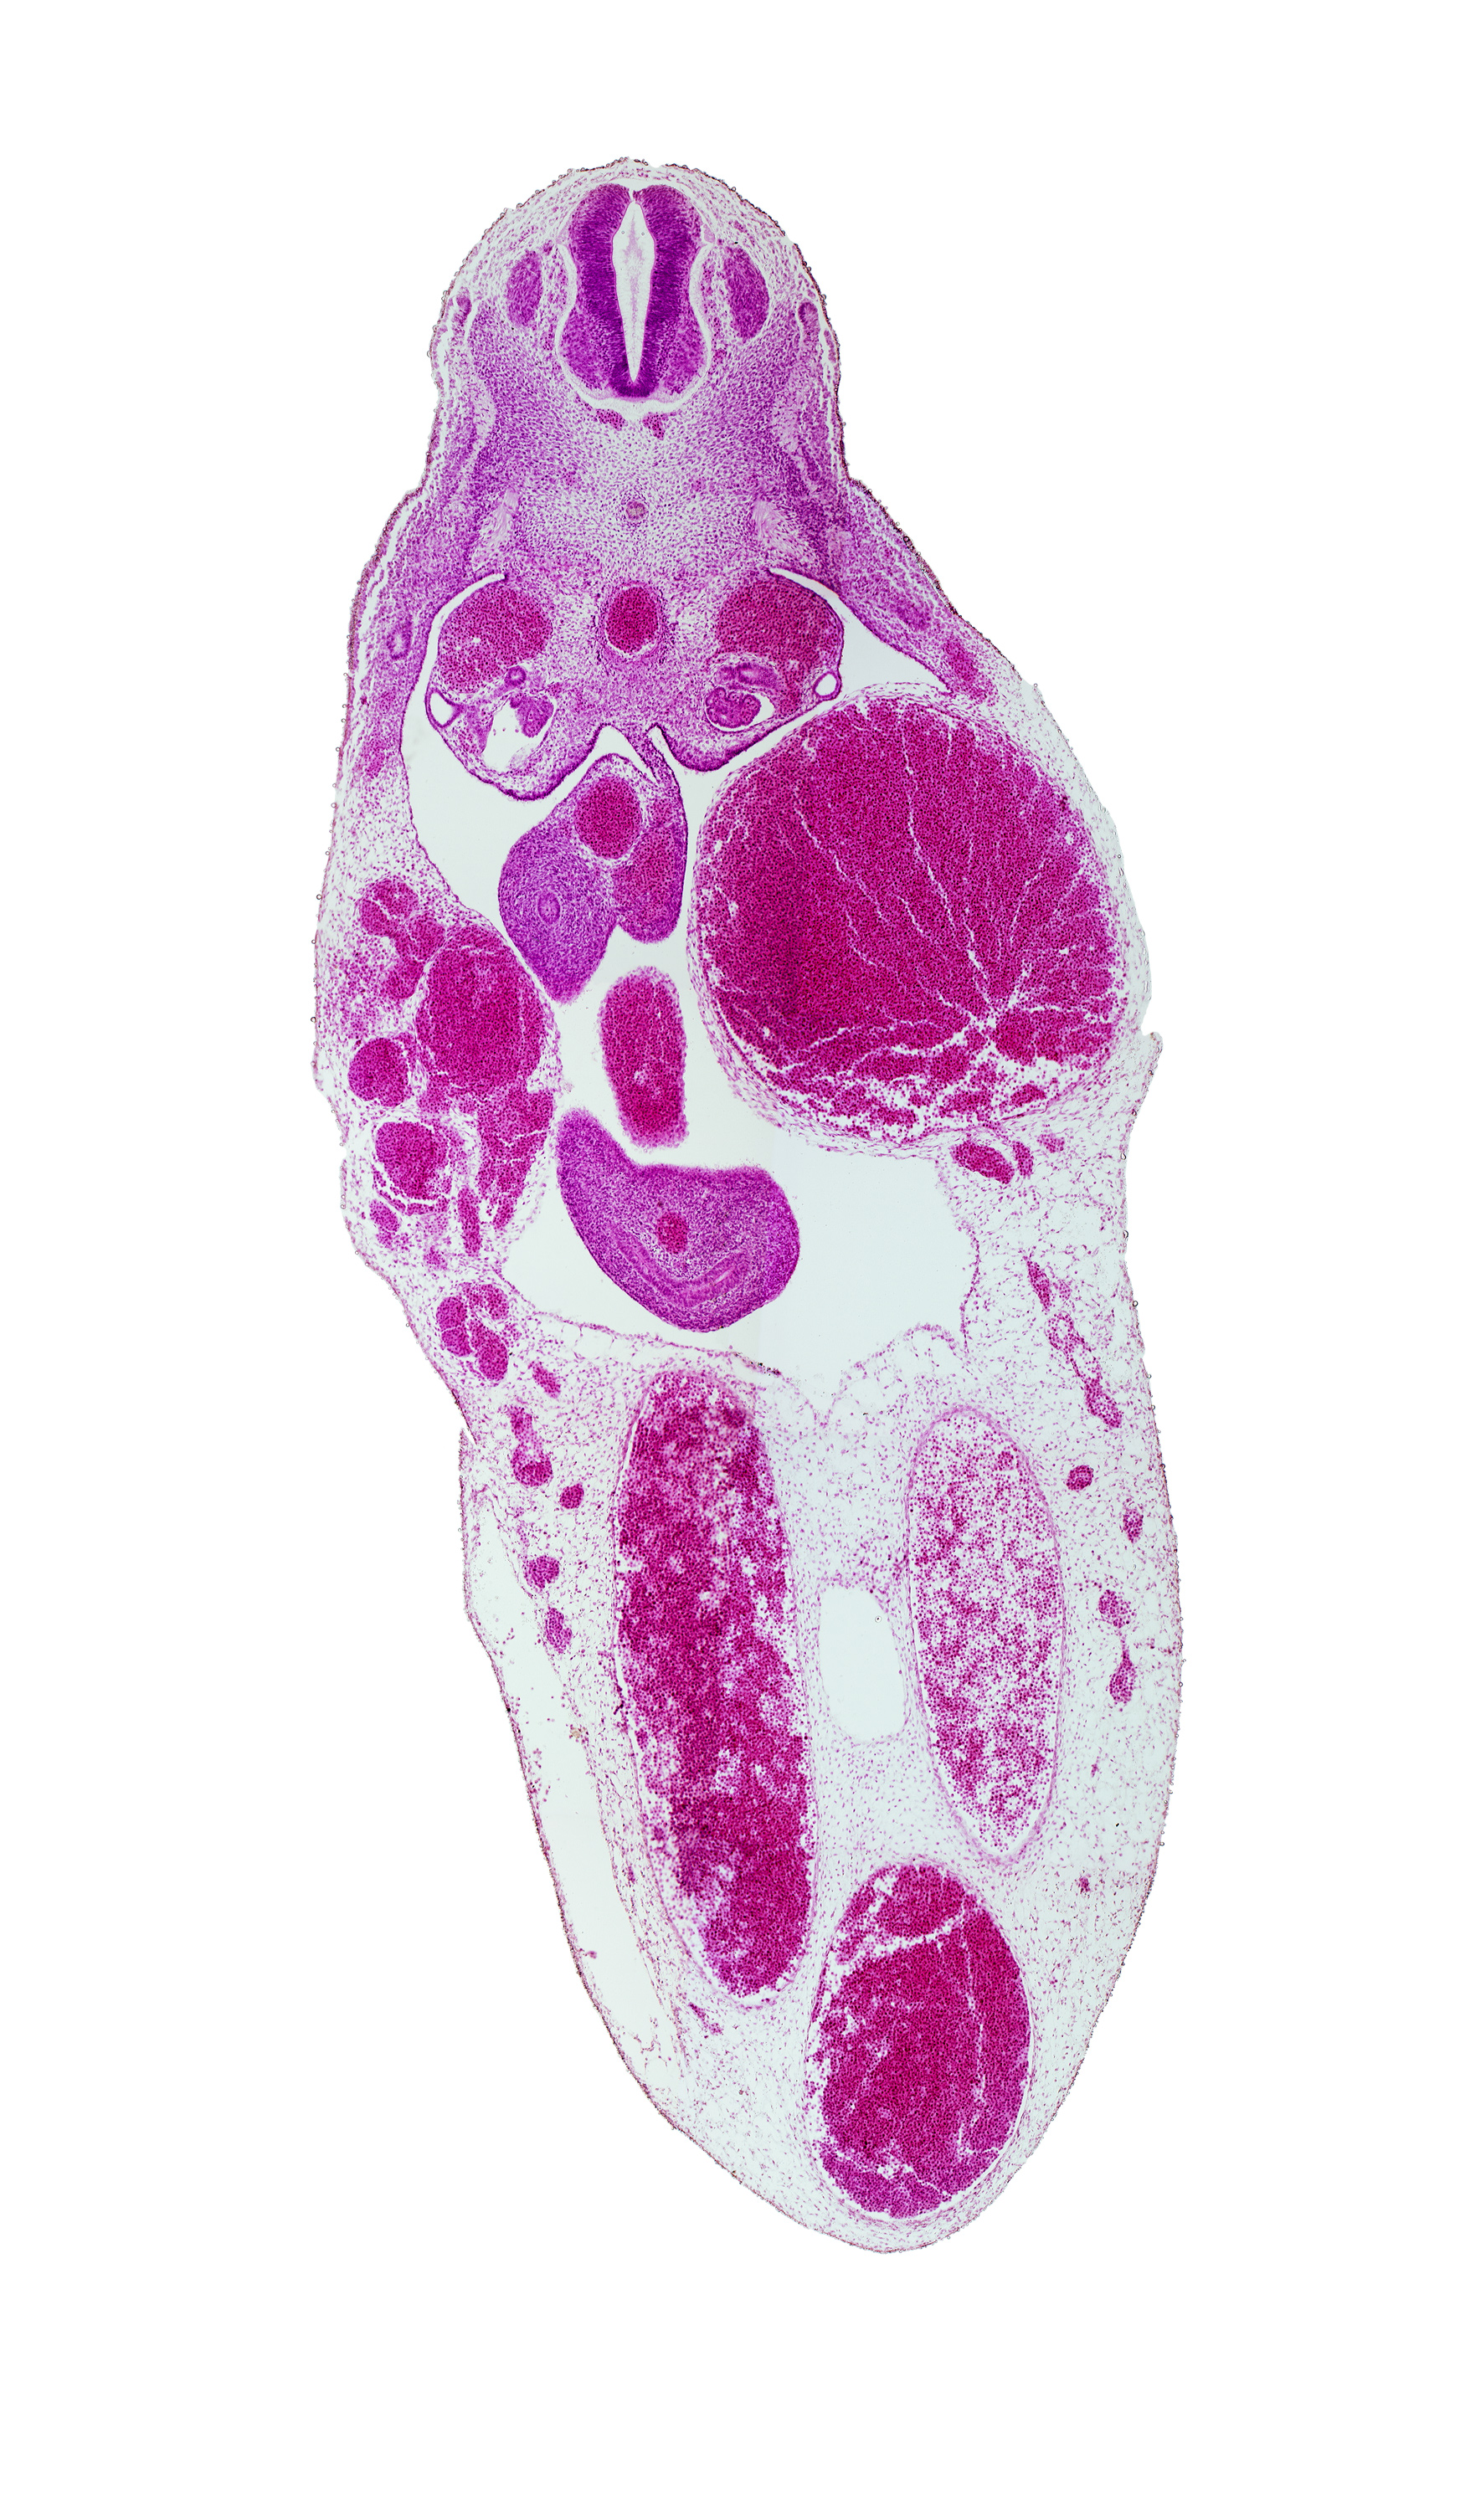

T-7 spinal ganglion, aorta, gonadal ridge, left umbilical artery, left umbilical vein (congested), mesonephric duct, midgut, postcardinal vein, right umbilical artery, superior mesenteric artery, umbilical vein

Carnegie Embryo #721   |   Location: 20-02-04

Keywords: T-7 spinal ganglion, aorta, gonadal ridge, left umbilical artery, left umbilical vein (congested), mesonephric duct, midgut, postcardinal vein, right umbilical artery, superior mesenteric artery, umbilical vein